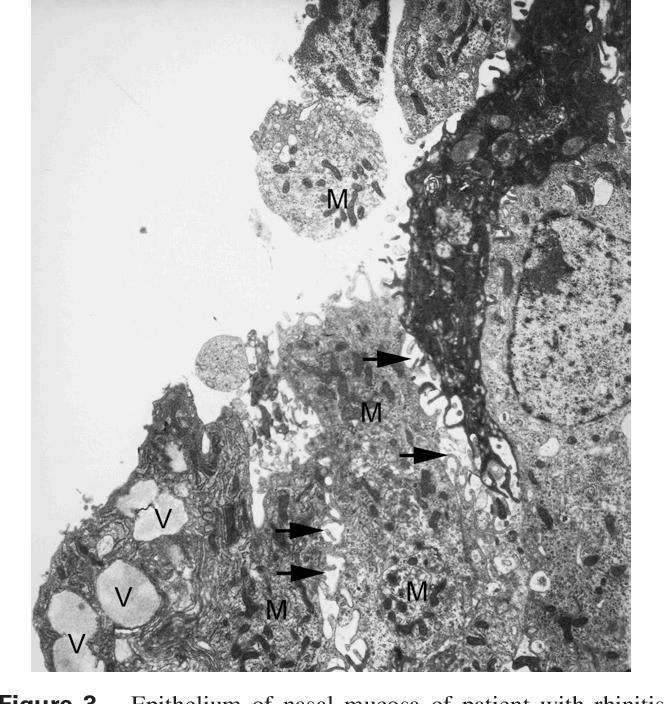

Fig 2 S Knipping, Epithelium of nasal mucosa of patient with rhinitis medicamentosa illustrated under electron microscope showing loss of cilia and damaged epithelial cells; intraepithelial numerous vacuoles (V) and mitochondria (M); dilated intercellular spaces (arrows), 2008 (Original magnification 7,000 )